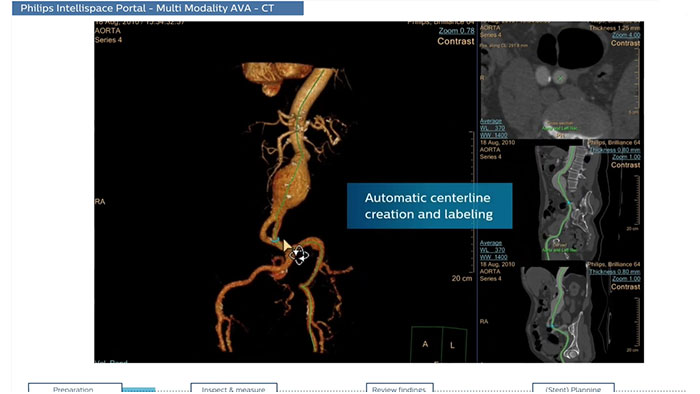

Multi Modality Advanced Vessel Analysis comprehensive vascular planning

The application is designed to examine and quantify different types of vascular lesions from CT and MR, providing modes of inspection, labeling of different vascular lesions, and customizable volume rendering.

CT Advanced Vessel Analysis (AVA) Stent Planning

Endovascular stent placement

CT Advanced Vessel Analysis (AVA) Stent Planning includes multiple preset and user-defined options to gain detailed information for use in stent planning.

Benefits

- The application allows you to export customized results to external reporting systems.

Multi Modality Advanced Vessel Analysis (AVA)

Comprehensive vascular analysis planning

Designed to examine and quantify different types of vascular lesions from CTA and MRA scans. It accommodates different modes of inspection, allows labeling different vascular lesions, and helps navigating through multiple findings.

Demonstrated to reduce the post-processing time by 50% when compared to manual Head & Neck CT angiography (CTA) analysis*.

Benefits

- Ability to choose which Head & Neck Bone Removal method to be used (Standard vs. Smooth).

- Customizable Volume rendering “smoothness” for the 3D Head & Neck vascular structure using a smoothness control.

* Ardley N et al. Efficacy of a new post processing workflow for CTA head and neck. ECR 2013 / C-1760.